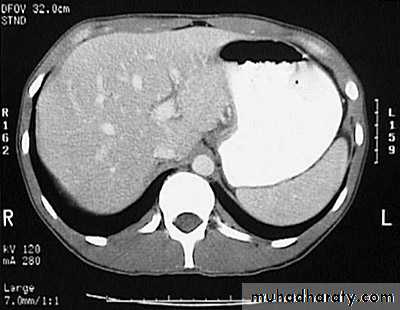

Secondary metastasis in the liver

Multiple rounded hypo density areas of different density , shape & different size .

Pattern of enhancement is either uniform , target or bulls eye pattern .

Hepato megaly .

Secondary metastasis within the liver